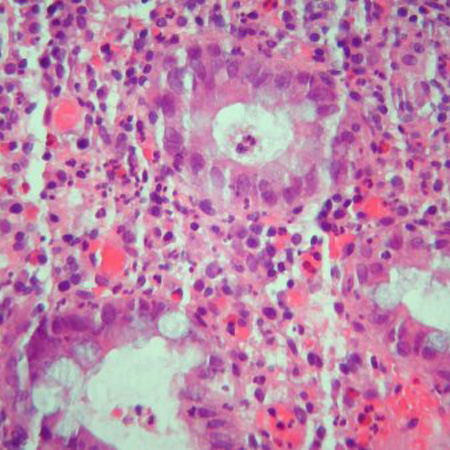

biópsia tecidual

Biópsias segmentares do cólon e do íleo devem ser obtidas para avaliar a evidência microscópica de doença de Crohn (DC).[70] As características microscópicas que ajudam a distinguir a colite ulcerativa da DC incluem granulomas, a alteração da arquitetura e a distribuição da doença.[81] A inflamação granulomatosa é, entretanto, relatada em uma minoria de pacientes com DC (30% a 50%); ela não é necessária para o diagnóstico.[71][81][Figure caption and citation for the preceding image starts]: Inflamação significativa na parede do cólon, alargamento da submucosa e agregados linfoides densos na submucosaFornecido pelo Dr. Wissam Bleibel, Dr. Bishal Mainali, Dr. Chandrashekhar Thukral e Dr. Mark A. Peppercorn, os autores anteriores deste tópico [Citation ends].

[Figure caption and citation for the preceding image starts]: Granulomas em um paciente com doença de Crohn; observe o agregado de histiócitos epitelioidesFornecido pelo Dr. Wissam Bleibel, Dr. Bishal Mainali, Dr. Chandrashekhar Thukral e Dr. Mark A. Peppercorn, os autores anteriores deste tópico [Citation ends].

[Figure caption and citation for the preceding image starts]: Criptite e abscessos em cripta com distorção morfológica das criptas acompanhadas de inflamação e plasmócitos e linfócitos abundantesFornecido pelo Dr. Wissam Bleibel, Dr. Bishal Mainali, Dr. Chandrashekhar Thukral e Dr. Mark A. Peppercorn, os autores anteriores deste tópico [Citation ends].

Biópsias de mucosa não comprometida ajudam a identificar a extensão da doença histológica.[71] Se tuberculose estiver sendo cogitada, o tecido das biópsias ileocecais poderá ser testado quanto à presença de Mycobacterium tuberculosis.[69]

Resultado

biópsias da mucosa do intestino demonstram o envolvimento transmural com granulomas não caseosos